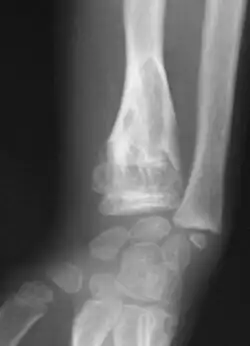

Abnormal bone growth such as shortening or thickening and deformity may be observed in patients of Ollier disease. These bone lesions are visible at birth using radiography but are usually not screened or examined for until clinical manifestations present during early childhood. However, some patients may exhibit no signs of any symptoms.[1] One study found thirteen to be the mean age of diagnosis in patients with Ollier disease. In an X-ray, there would normally be the presence of several homogeneous lesions of an oval or elongated shape with bone edges that are slightly thickened.[3] With age, these lesions may calcify and appear as diffusely minute spots or stippled. Fan-like septations or streaks would be indicative of the presence of several enchondromas. Early detection and consistent and repeated monitoring is important in order to prevent and treat any potential bone neoplasms.

X-ray showing calcified enchondromas localized in finger a 37-year-old patient affected with Ollier disease -

X-ray showing enchondromas localized in the humerus of a 37-year-old patient affected with Ollier disease -

X-ray showing enchondromas localized in the lower part of the radius of a 37-year-old patient affected with Ollier disease -